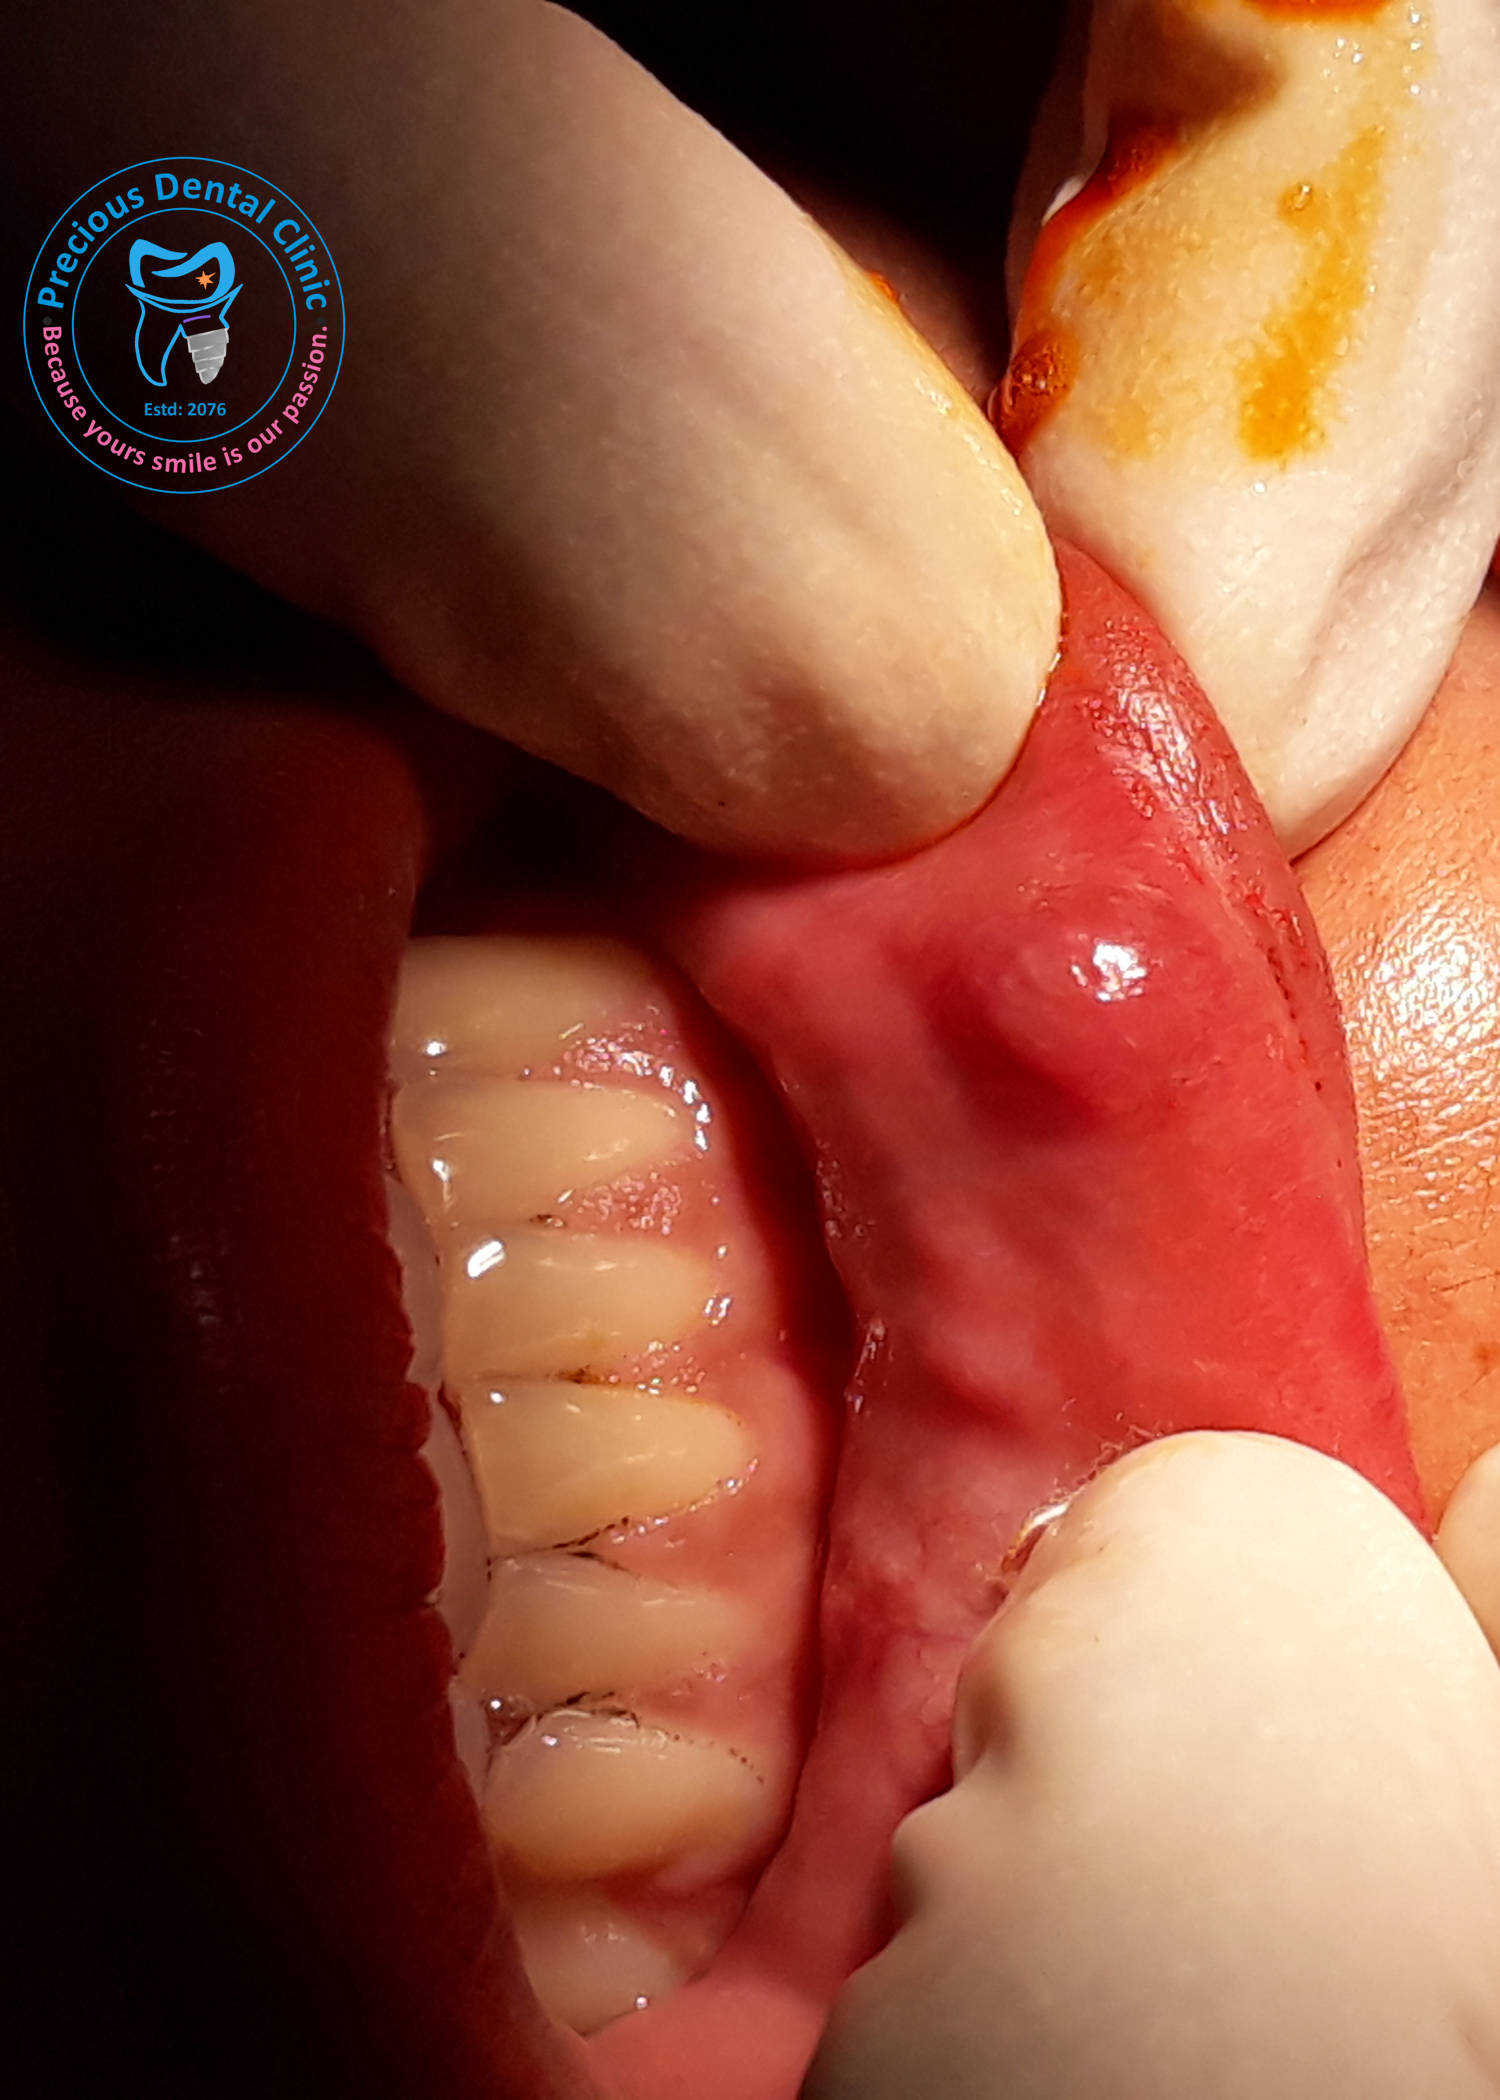

Collection of photos, here you will find the photos of doctor, services, environment and work.